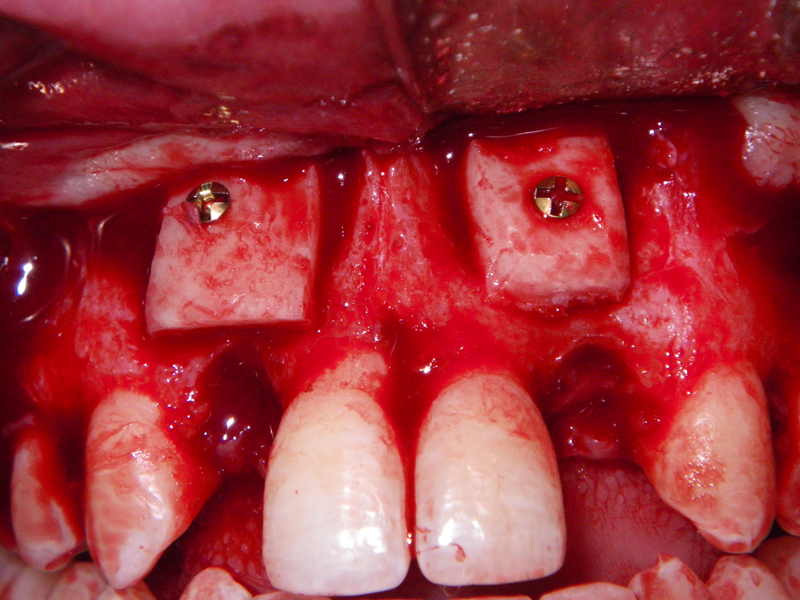

- Stage I: Implant placement/Sealing Screw

- Alveolar Ridge Augmentation

- Bone grafting – autogeneous, alogenic, xenogenic

- Blockgraft